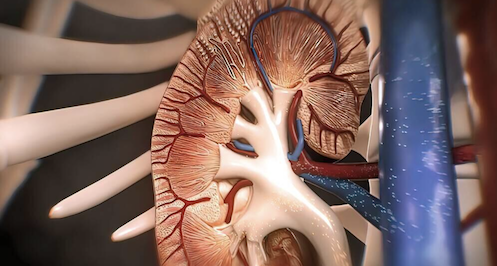

Nhưng nếu buổi sáng sau khi thức dậy bạn phát hiện mặt đặc biệt sưng, ấn vào không có độ đàn hồi thì đây có thể là dấu hiệu của bệnh thận.

Vì thận là cơ quan chuyển hóa nước và muối trong cơ thể con người, nếu thận gặp vấn đề thì nước và muối không thể chuyển hóa được, gây ra triệu chứng phù mặt.

Sau một đêm ngủ dậy, việc đầu tiên là đi vệ sinh để tống chất thải tích tụ trong cơ thể ra ngoài. Tuy nhiên, nếu sau khi ngủ dậy bạn thấy mình đi tiểu nhiều lần hơn một cách bất thường, tiểu rắt, màu nước tiểu bất thường, tiểu ra máu,… thì có thể liên quan đến bệnh thận. Đặc biệt khi mắc bệnh thận mãn tính, nước tiểu sẽ chứa một lượng lớn protein, hồng cầu, nitơ urê và các chất khác nên bệnh nhân thường có triệu chứng protein niệu.